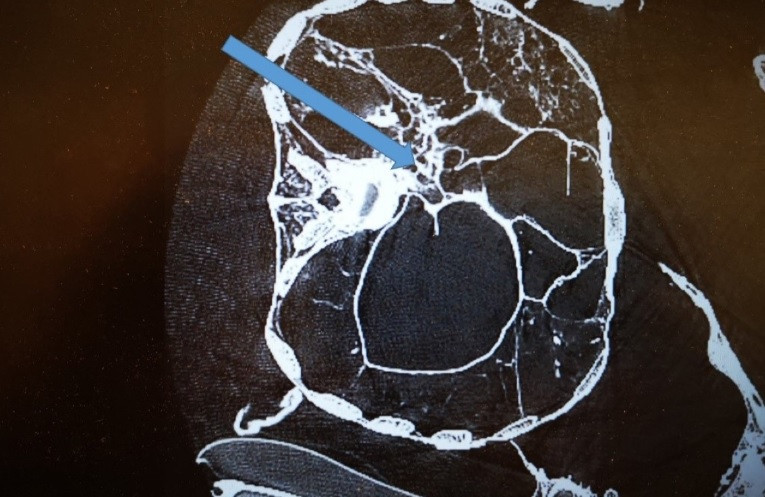

Từ các đặc điểm xương và kết quả phân tích xác ướp bằng phương pháp chụp cắt lớp vi tính 3D (3D-CT), nhóm nghiên cứu ước tính người đàn ông qua đời khi khoảng 20 - 25 tuổi, cao khoảng 1,72m.

Cụ thể, kết quả phân tích bằng 3D-CT chỉ ra người đàn ông trên tử vong do cú đánh chí mạng vào đầu và bị đâm vào lưng trong lúc đang đứng hoặc quỳ. Những vết thương nghiêm trọng này gây ra bởi một hoặc hai kẻ tấn công vào khoảng năm 996 - 1147.